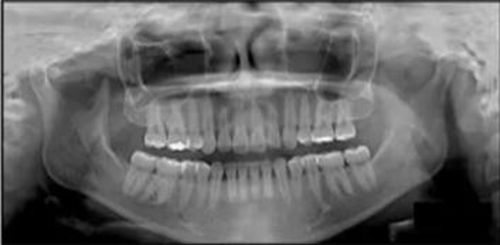

治療后全景片提示間隙得到關(guān)閉,除了左下頜第一前磨牙外牙根平行度可,無明顯骨及牙根吸收。(圖7)